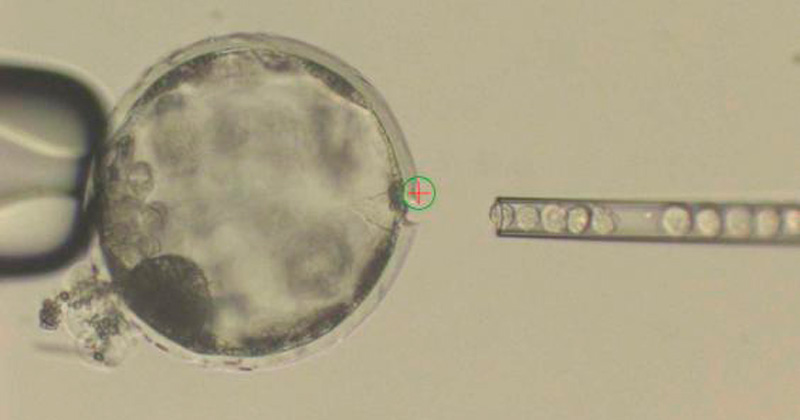

En un artículo publicado en la revista Cell se detalla que el logro es posible gracias a la combinación de técnicas con células madre y la edición genómica. En el experimento llevado a cabo, se inyectaron células madre humanas en embriones de cerdo en una etapa temprana para luego transferir el embrión híbrido a cerdas y proceder a la gestación.

El embarazo se interrumpió a los 28 días, el tiempo que necesitaban los autores para comprender cómo se mezclan las células de ambas especies.